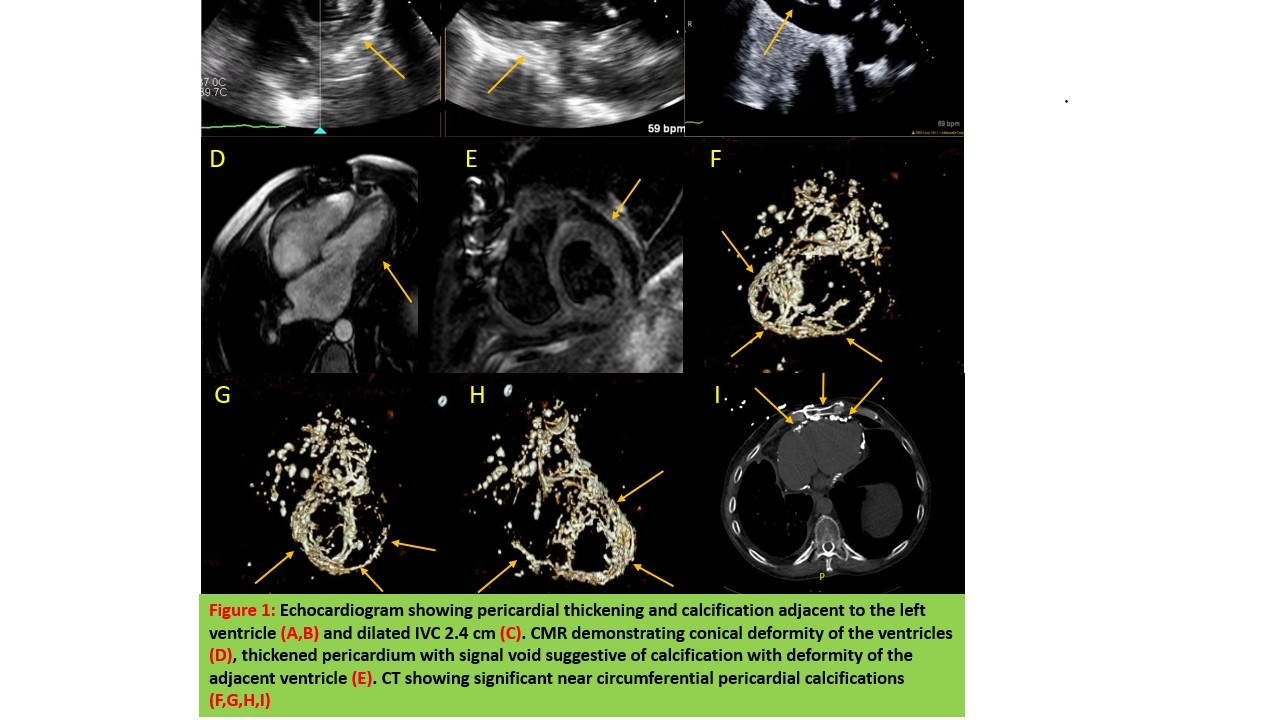

Abstract Body (Do not enter title and authors here): Clinical Presentation: A 62-year-old male with a complex medical history, including pulmonary sarcoidosis, diabetes, constrictive pericarditis post partial pericardial stripping, cirrhosis, and congestive heart failure, presented with signs and symptoms of volume overload. Despite increasing diuretics and previous paracentesis, his condition continued to deteriorate. There were raising concerns for constrictive pericarditis due to cardiac sarcoidos. Echocardiography (TEE) showed pericardial thickening and calcification adjacent to the left ventricle and dilated IVC 2.4 cm (TTE). Cardiac magnetic resonance imaging (CMR) demonstrated conical deformity of the ventricles, thickened pericardium with signal void suggestive of calcification. Computed Tomography (CT) showed significant near circumferential pericardial calcifications. Subsequent catheterization confirmed constriction and identified a right coronary artery lesion. Following this, the patient underwent a redo pericardiectomy and coronary artery bypass grafting, at the Cleveland Clinic. However, his post-operative course was marked by complex challenges, including multi-organ dysfunction, the need for tracheostomy, feeding tube, renal replacement therapy, and recurrent ascites. Despite intensive care, his condition did not improve, leading to a transition to comfort care and eventually the patient passed away in December 2023.